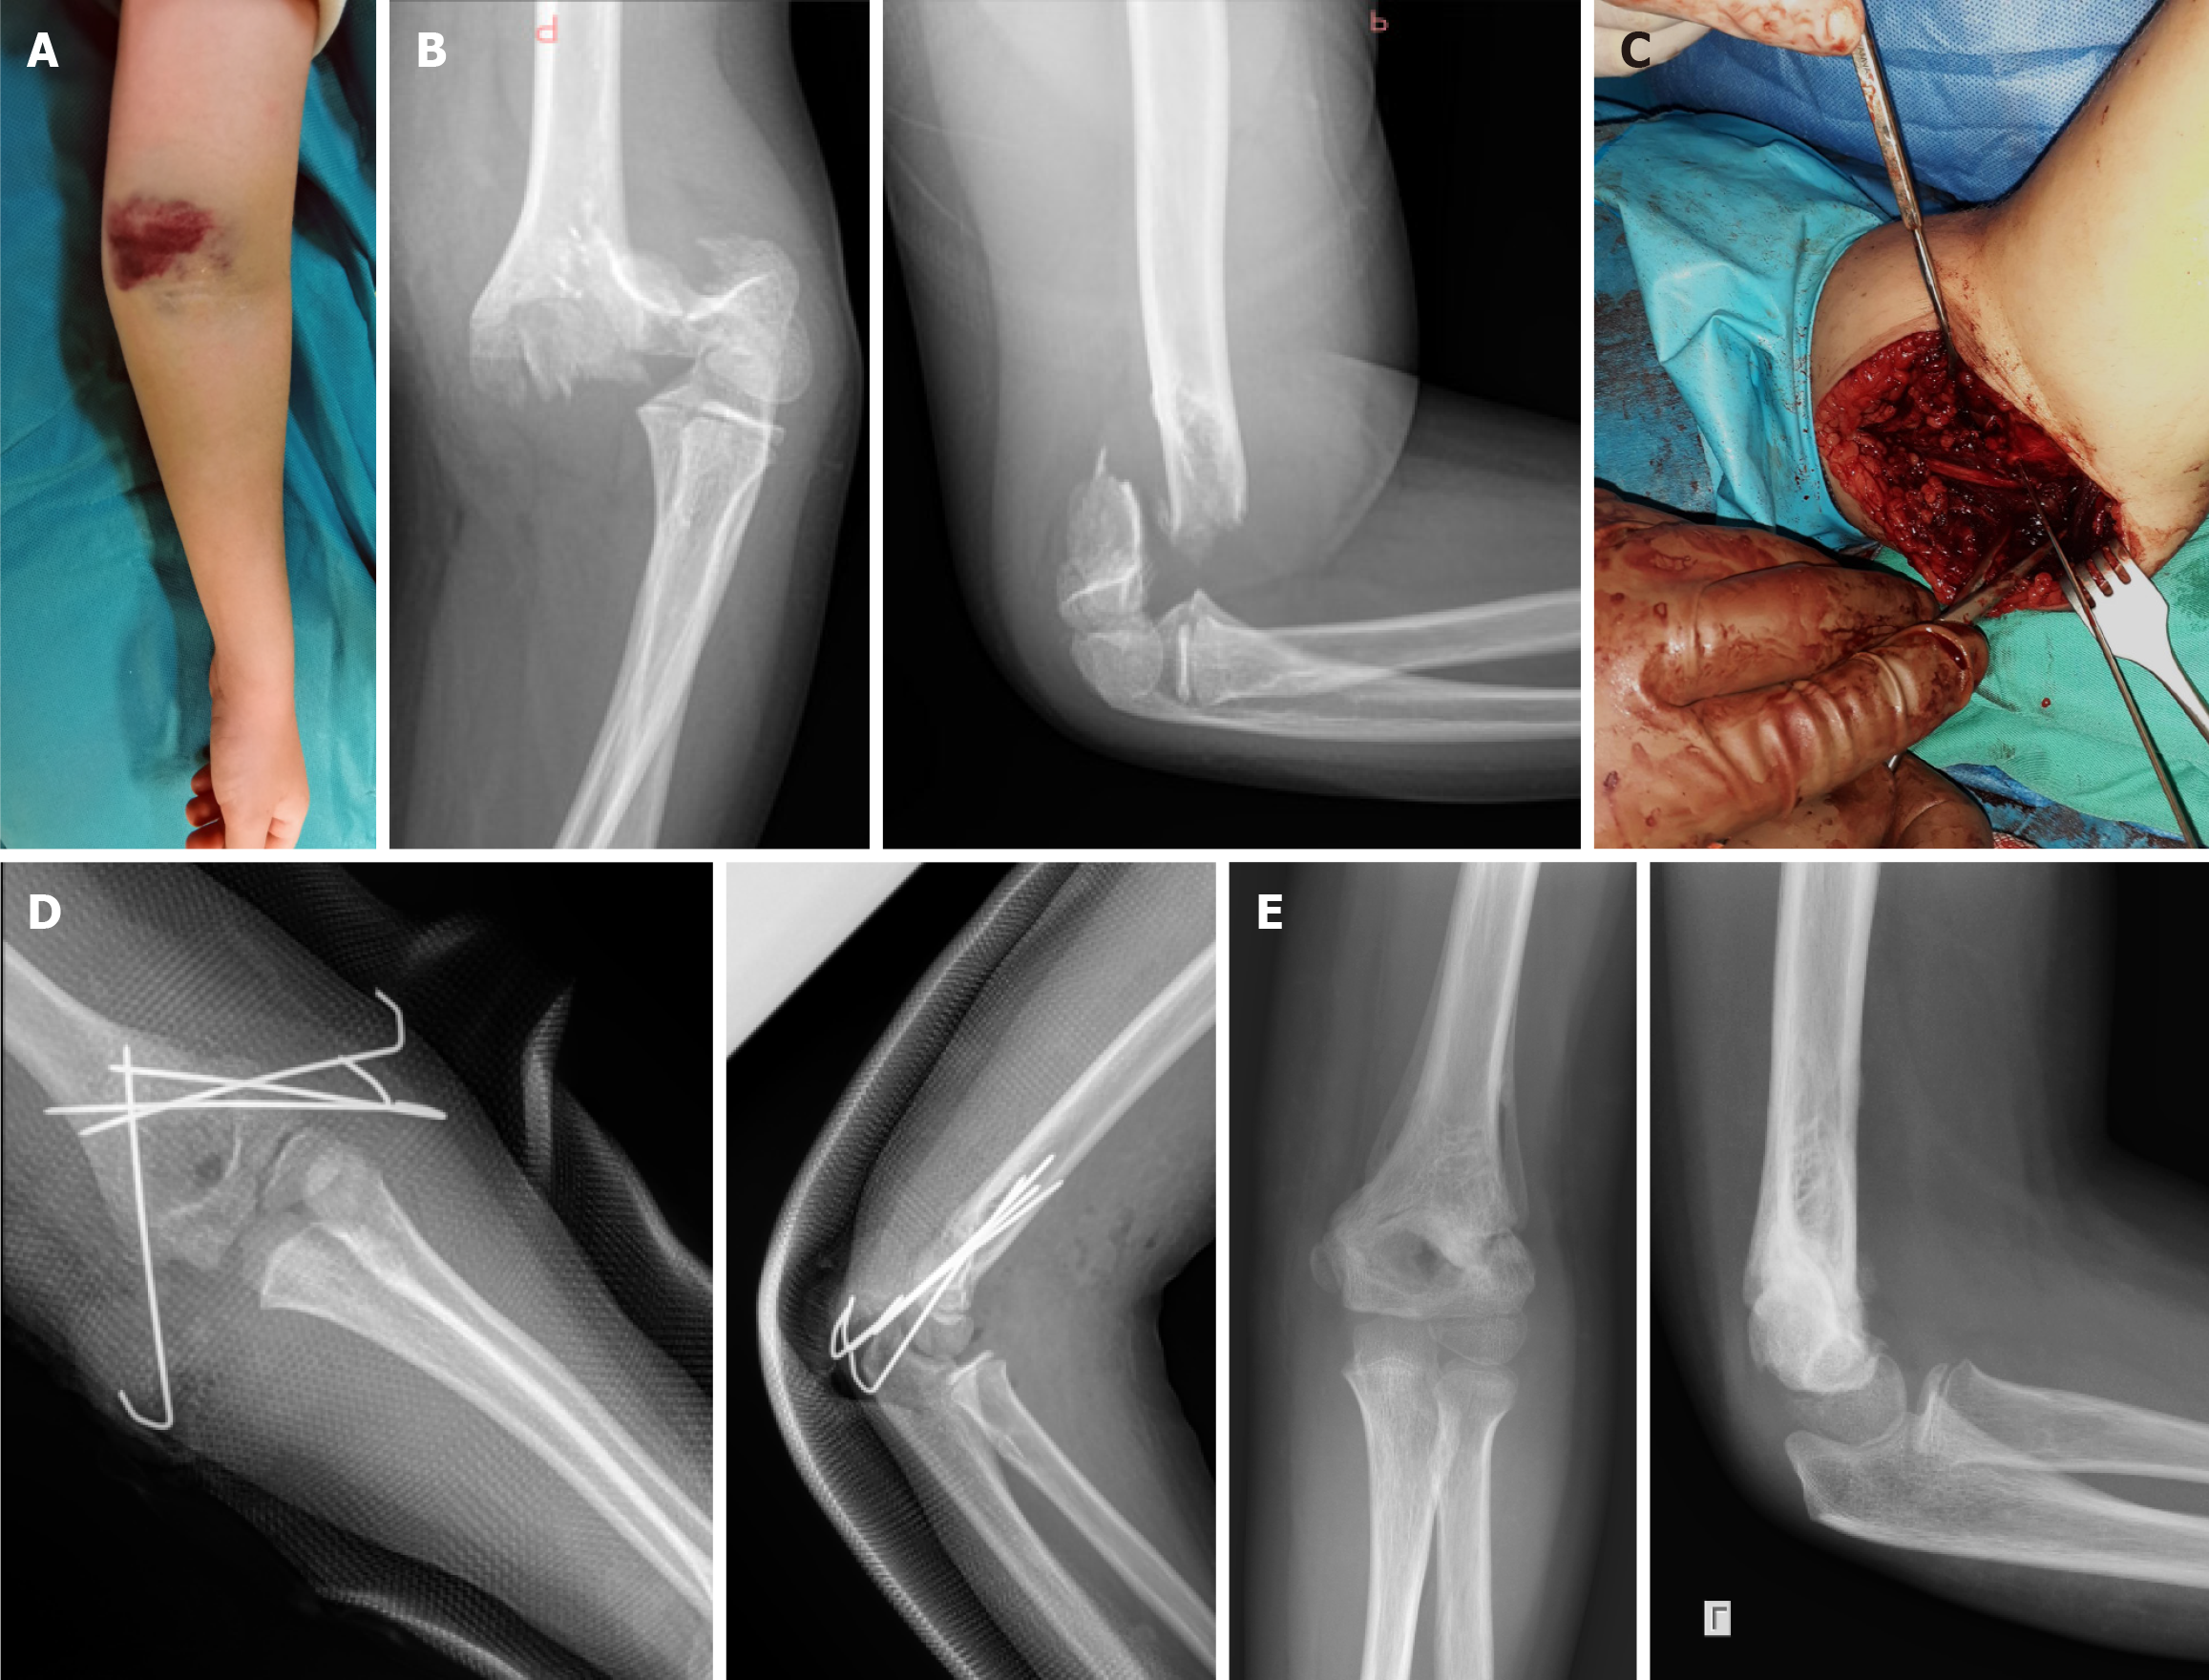

Figure 2 Significant anterior elbow haematoma, pink pulseless hand and anterior interosseous nerve palsy in an 8-year-old male with a Gartland type IV supracondylar humeral.

A: Clinical presentation; B: Radiological examination; C: Open reduction by lateral approach was unsuccessful due to periosteum and flexor muscles interposition on medial side requiring an enlarged medial approach and ulnar nerve exploration and protection; D: Four K-wires were applied (3 Lateral and 1 medial); E: K-wires were removed 5 weeks post-operatively. Normal pulses were palpable in hand 12 hours post-operatively and anterior interosseous nerve palsy recovered in 6 weeks.